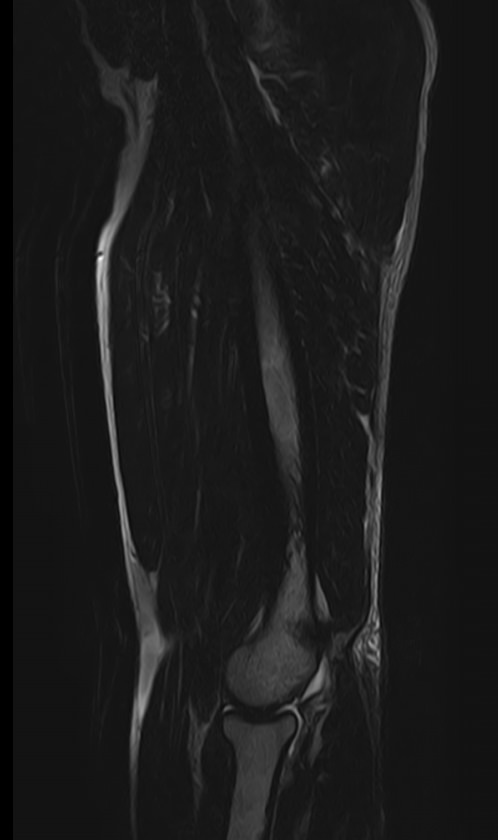

Магнитно-резонансная томография применяется для обследования мягких тканей верхних и нижних конечностей, включая кожу, подкожно-жировую клетчатку, мышцы, фасции, межфасциальные пространства, сухожилия, связки, сосудистую систему, лимфоузлы и лимфатические протоки, нервные волокна, надкостницу и костный мозг.

Кроме того, имеет значение показатель индукции магнитного поля томографа. Наша клиника оснащена современным высокопольным томографом последнего поколения TOSHIBA VANTAGE TITAN 1,5 Тесла. Высокая индукция магнитного поля обеспечивает повышенную четкость изображений при обследовании мягких тканей конечностей. За счет послойного сканирования в различных плоскостях с шагом от 1 мм и последующего преобразования данных в объемные изображения томограф обеспечивает выявление мельчайших изменений в тканях. Это позволяет проводить диагностику различных заболеваний на самых ранних стадиях.